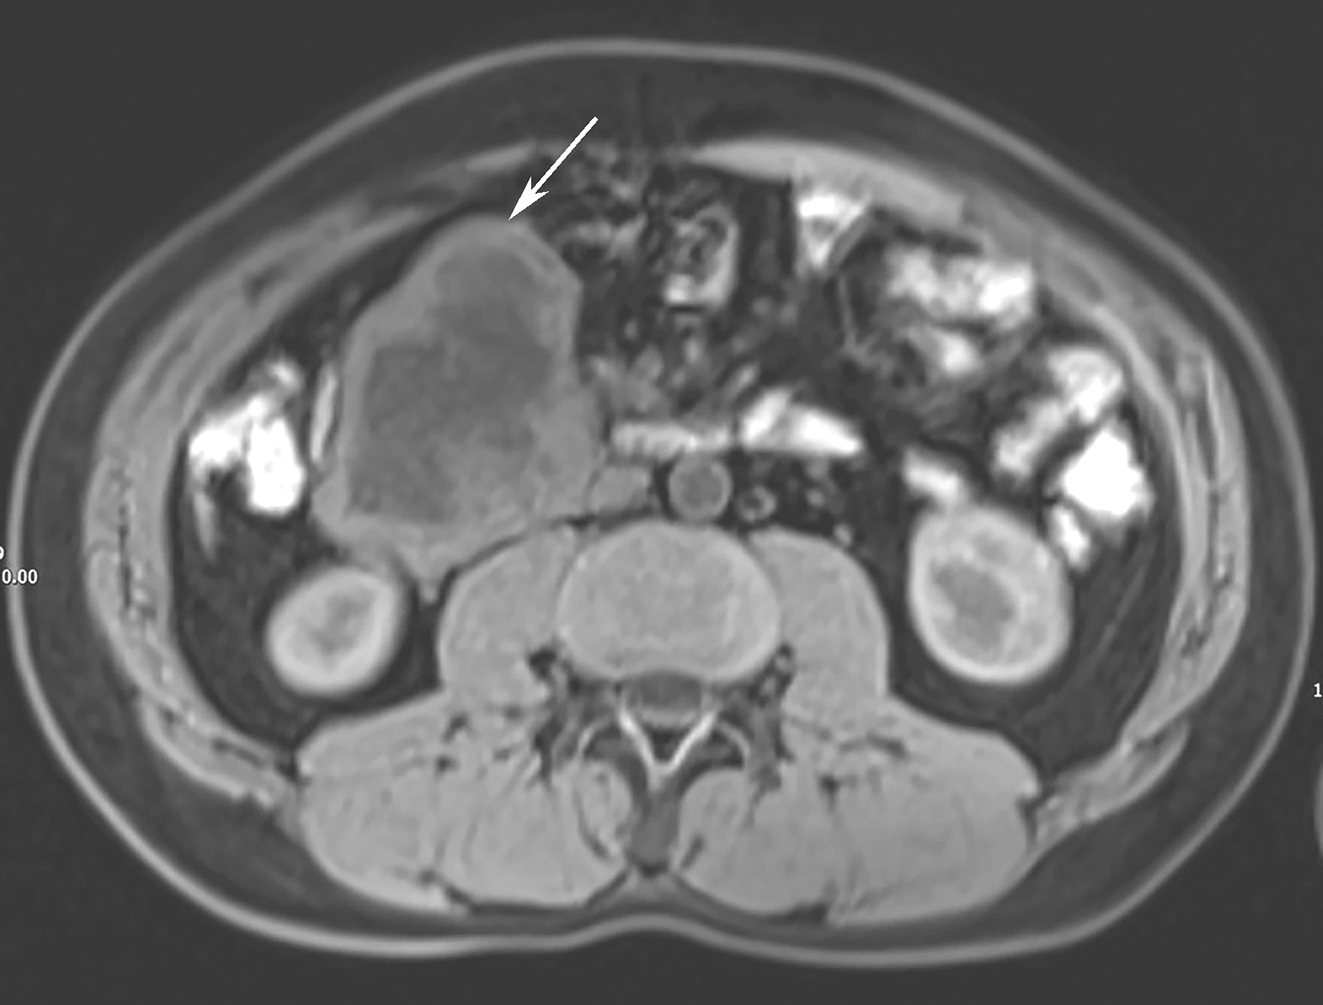

患者,男性,41岁,于2017年11月8日因“黑便2天”就诊于当地医院。当地医院行腹部CT检查,报告示:十二指肠水平部软组织肿块,大小约7.0cm×5.5cm,考虑为胃肠间质瘤,周围数枚淋巴结肿大,考虑转移可能。患者为求进一步诊治,赴华中科技大学同济医学院附属协和医院就诊,行穿刺活检示:送检(十二指肠降部占位穿刺活检组织)全部取材制片,镜下主要为血细胞及纤维素样渗出物,其内夹杂少许梭形细胞巢,免疫组织化学染色示该细胞巢CD117(+),DDG-1(+),CD34(-),SMA(+),S-100(-),SDHB(+),Ki-67(个别 +),免疫表型符合胃肠间质瘤。肝脾MRI平扫+增强示:①肝内多发类圆形稍长T1,稍长T2信号影,较大者位于肝左叶外侧段包膜下,大小约2.3cm×2.2cm×1.3cm,钆塞酸二钠增强扫描动脉期病灶明显强化,部分病灶边缘环形强化,肝胆期呈稍低信号,弥散未见明显受限,考虑海绵状血管瘤;②胆胰脾未见明显异常,建议复查;③扫描所及十二指肠降部走行区见混杂信号团块影(图1)。

图1 十二指肠降部走行区见混杂信号团块影